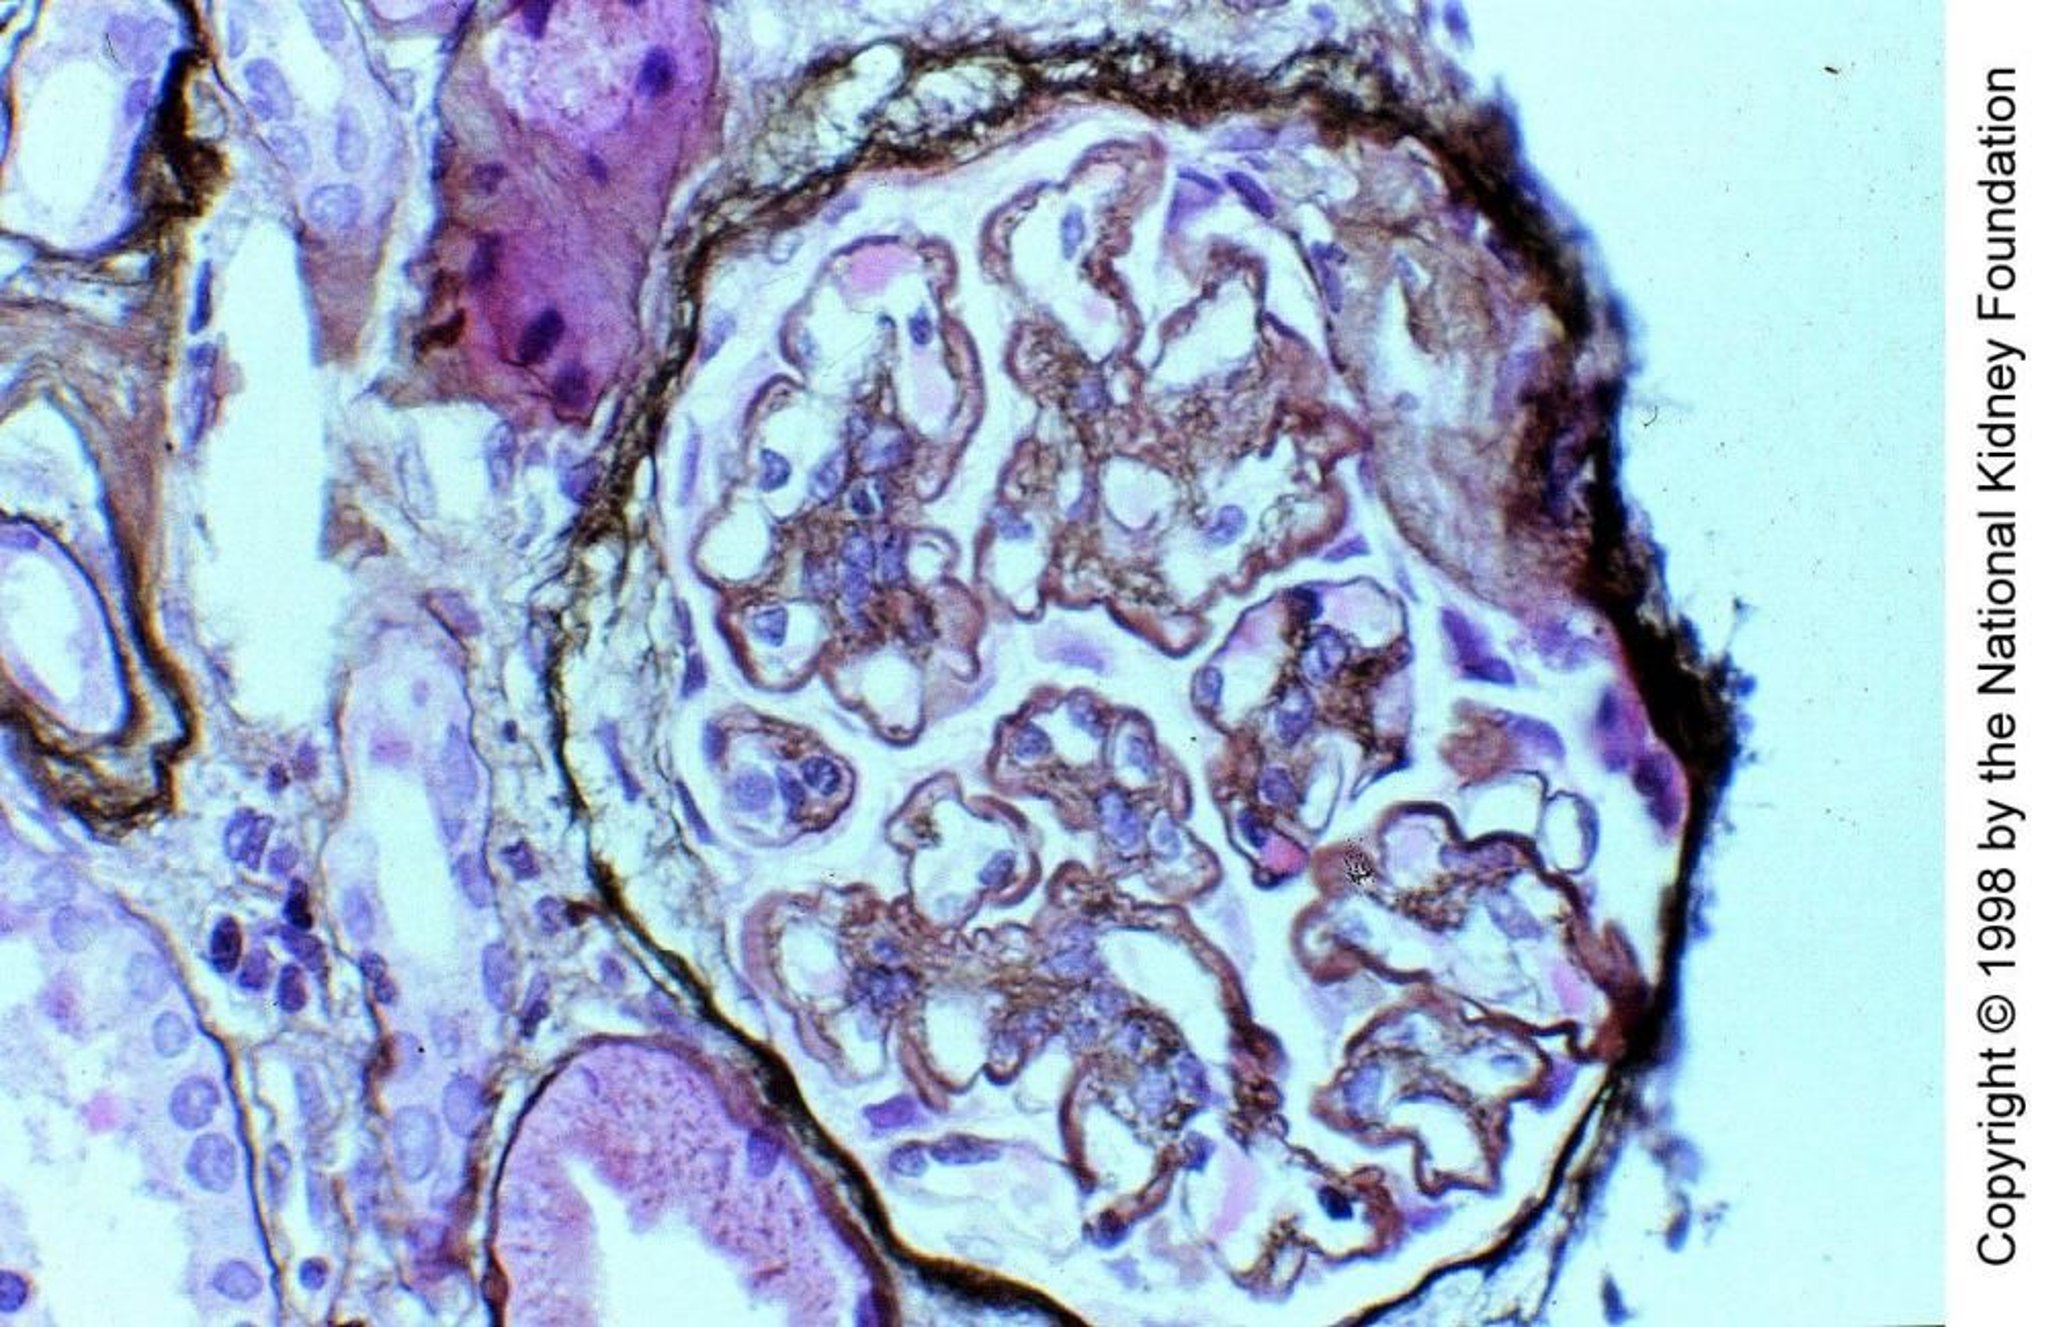

Мембранопролиферативный гломерулонефрит, опосредованный комплементом

При мембранозно-пролиферативном гломерулонефрите, опосредованном комплиментом (МПГН) II типа, C3-нефритогенном факторе, аутоиммунное антитело IgG, которое функционирует подобно пропердину, непосредственно расщепляя C3 до С3b, активирует комплемент через альтернативный путь в пределах стенок гломерулярных капилляров и мезангия. Отложения С3 частично замещают компоненты темной пластинки базальной мембраны, утолщая ее и придавая характерный вид «связки колбасы» (импрегнация солями серебра по Джонсу, ×400).

Image provided by Agnes Fogo, MD, and the American Journal of Kidney Diseases' Atlas of Renal Pathology (see www.ajkd.org).